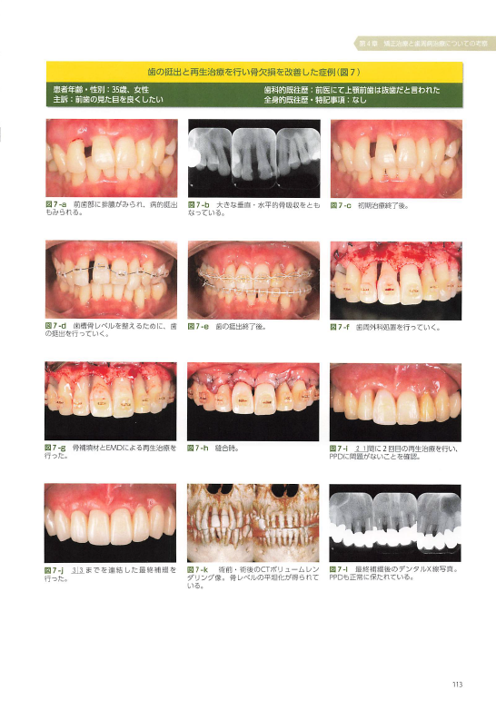

ニーズ3:40代以降で「歯周病が進行」している場合の矯正

40代~60代の方が矯正治療を希望されることも最近は増えてきました。お口の状態に問題がない場合は通常の矯正治療を行いますが、この年齢になると多くの方が「歯周病」になっていることが多くあります。歯周病の状態のまま矯正治療をすると矯正治療はうまくいかないため、まずは歯周病を改善してから治療を開始します。

また、歯周病の進行がかなり進行している場合、見た目も悪化しているため、そのまま矯正治療を行ったとしてもキレイにならないことがあります。そこで当院では、歯周病と矯正治療の他、セラミックの被せ物やケースによってはインプラントを併用し、お口全体の審美性を回復させる治療も行っています。

この総合的な治療を行うことで、口元が綺麗になる他、歯周病の再発防止(歯周ポケットを浅くする)、適切な噛み合わせの調整も可能になるため、お口全体の健康にもつながります。

このような治療は、当院の担当医である理事長はとても得意としています。このケースに関して、海外での発表や書籍の執筆も行っています。